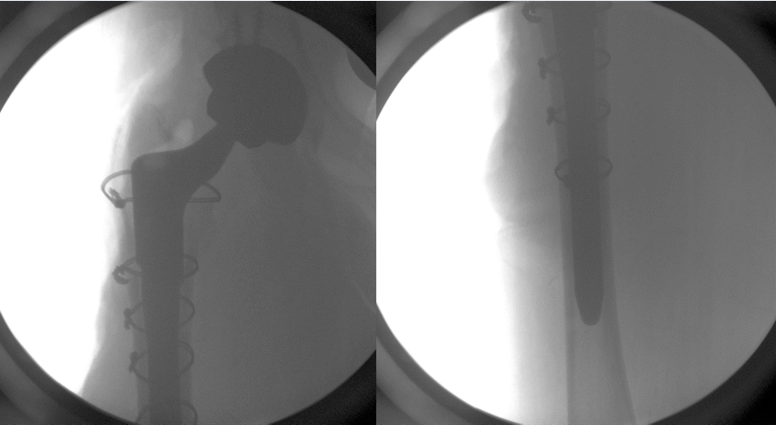

what is this